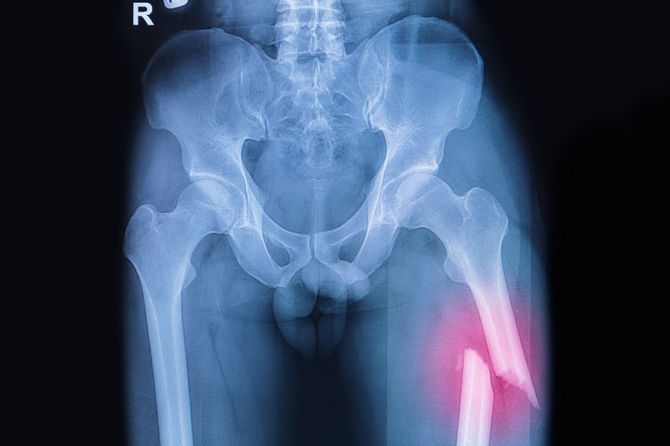

2019年6月。自宅で寝ていた母親が、起き上がるときにバランスを崩し、後ろに倒れ、そのまま起き上がれなくなる。ちょうど南野さんが不在だったため、母親は携帯電話で南野さんに連絡。急いで帰ると、母親は横たわったままで動けず、痛みも訴える。南野さんが救急車を呼ぶと、運良く父親が入院している病院へ運ばれた。そこは母親が定期的に抗がん剤治療を受けている病院だったので、都合が良かった。母親は大腿骨を骨折しており、そのまま入院になる。